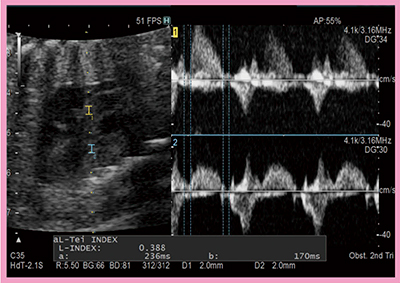

2)Tei indexの計測*

Tei indexは,胎児の心室の収縮能と拡張能の総合指標である。胎児管理においては,左心系はもとより右心系の機能が非常に重要であるが,Tei indexは両心室で計測できるため,右心室優位の胎児評価にも有用である。一方,Tei indexの計測に当たり,左心室は同一心周期で流入波形と流出波形を計測できるのに対し,右心室では不可能なほか,等容収縮能(ICT),等容拡張能(IRT)の個別の時間計測が従来法(Single Doppler法)では不可能であった。しかし,Dual Gate Doppler(PW法-PW法)では,流入波形と流出波形を一度に測定できるため心拍数の変動がなく,しかも,ICT,IRTの個別の測定が可能となる(図4)。このように,Dual Gate Dopplerは右心系の評価にも有用であると考えている。

図4 Dual Gate DopplerによるTei index計測